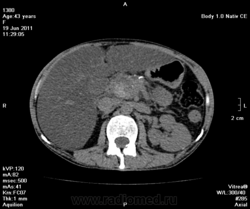

на фоне хр.калькулезного панкреатита опухоль головки поджелудочной железы, распространение на ворота печени, очень подозрительно на инвазию портальной вены и портальную гипертензию. Печень увеличена, гиподенсна, и если не ошибаюсь, цирроз.

Да, цирроз выставил, хотя конечно не такой уж он и показательный, нежели обычно с правильной атрофией и бугристыми контурами. На счет портальной вены тоже засомневался (на нативе прям как одно целое) и рекомендовал контраст, хотя, наверное, тут скорее эгоистический интерес.

хорошо протокол далеко не ушел.. только что еще раз решил посмотреть (нужно быть повнематочней.. в отпуск пора-( ):

Без контраста только гадать. Может, киста, может, и нет.

По-моему в печени жировой гепатоз. А контрастирование в этом случае обязательно.

Как прилежный ученик, я понимаю Вас, что основных то признаков нет - как со стороны селезенки (должного проявления портальной гипертензии), снижение плотности паренхимы печени (хотя фиброзные тяжи и тем более узлы должны бы давать повышенную плотность), отсутствие асцита! или хотя бы малого количества жидкости, отсутствие атрофических изменений и т.д...